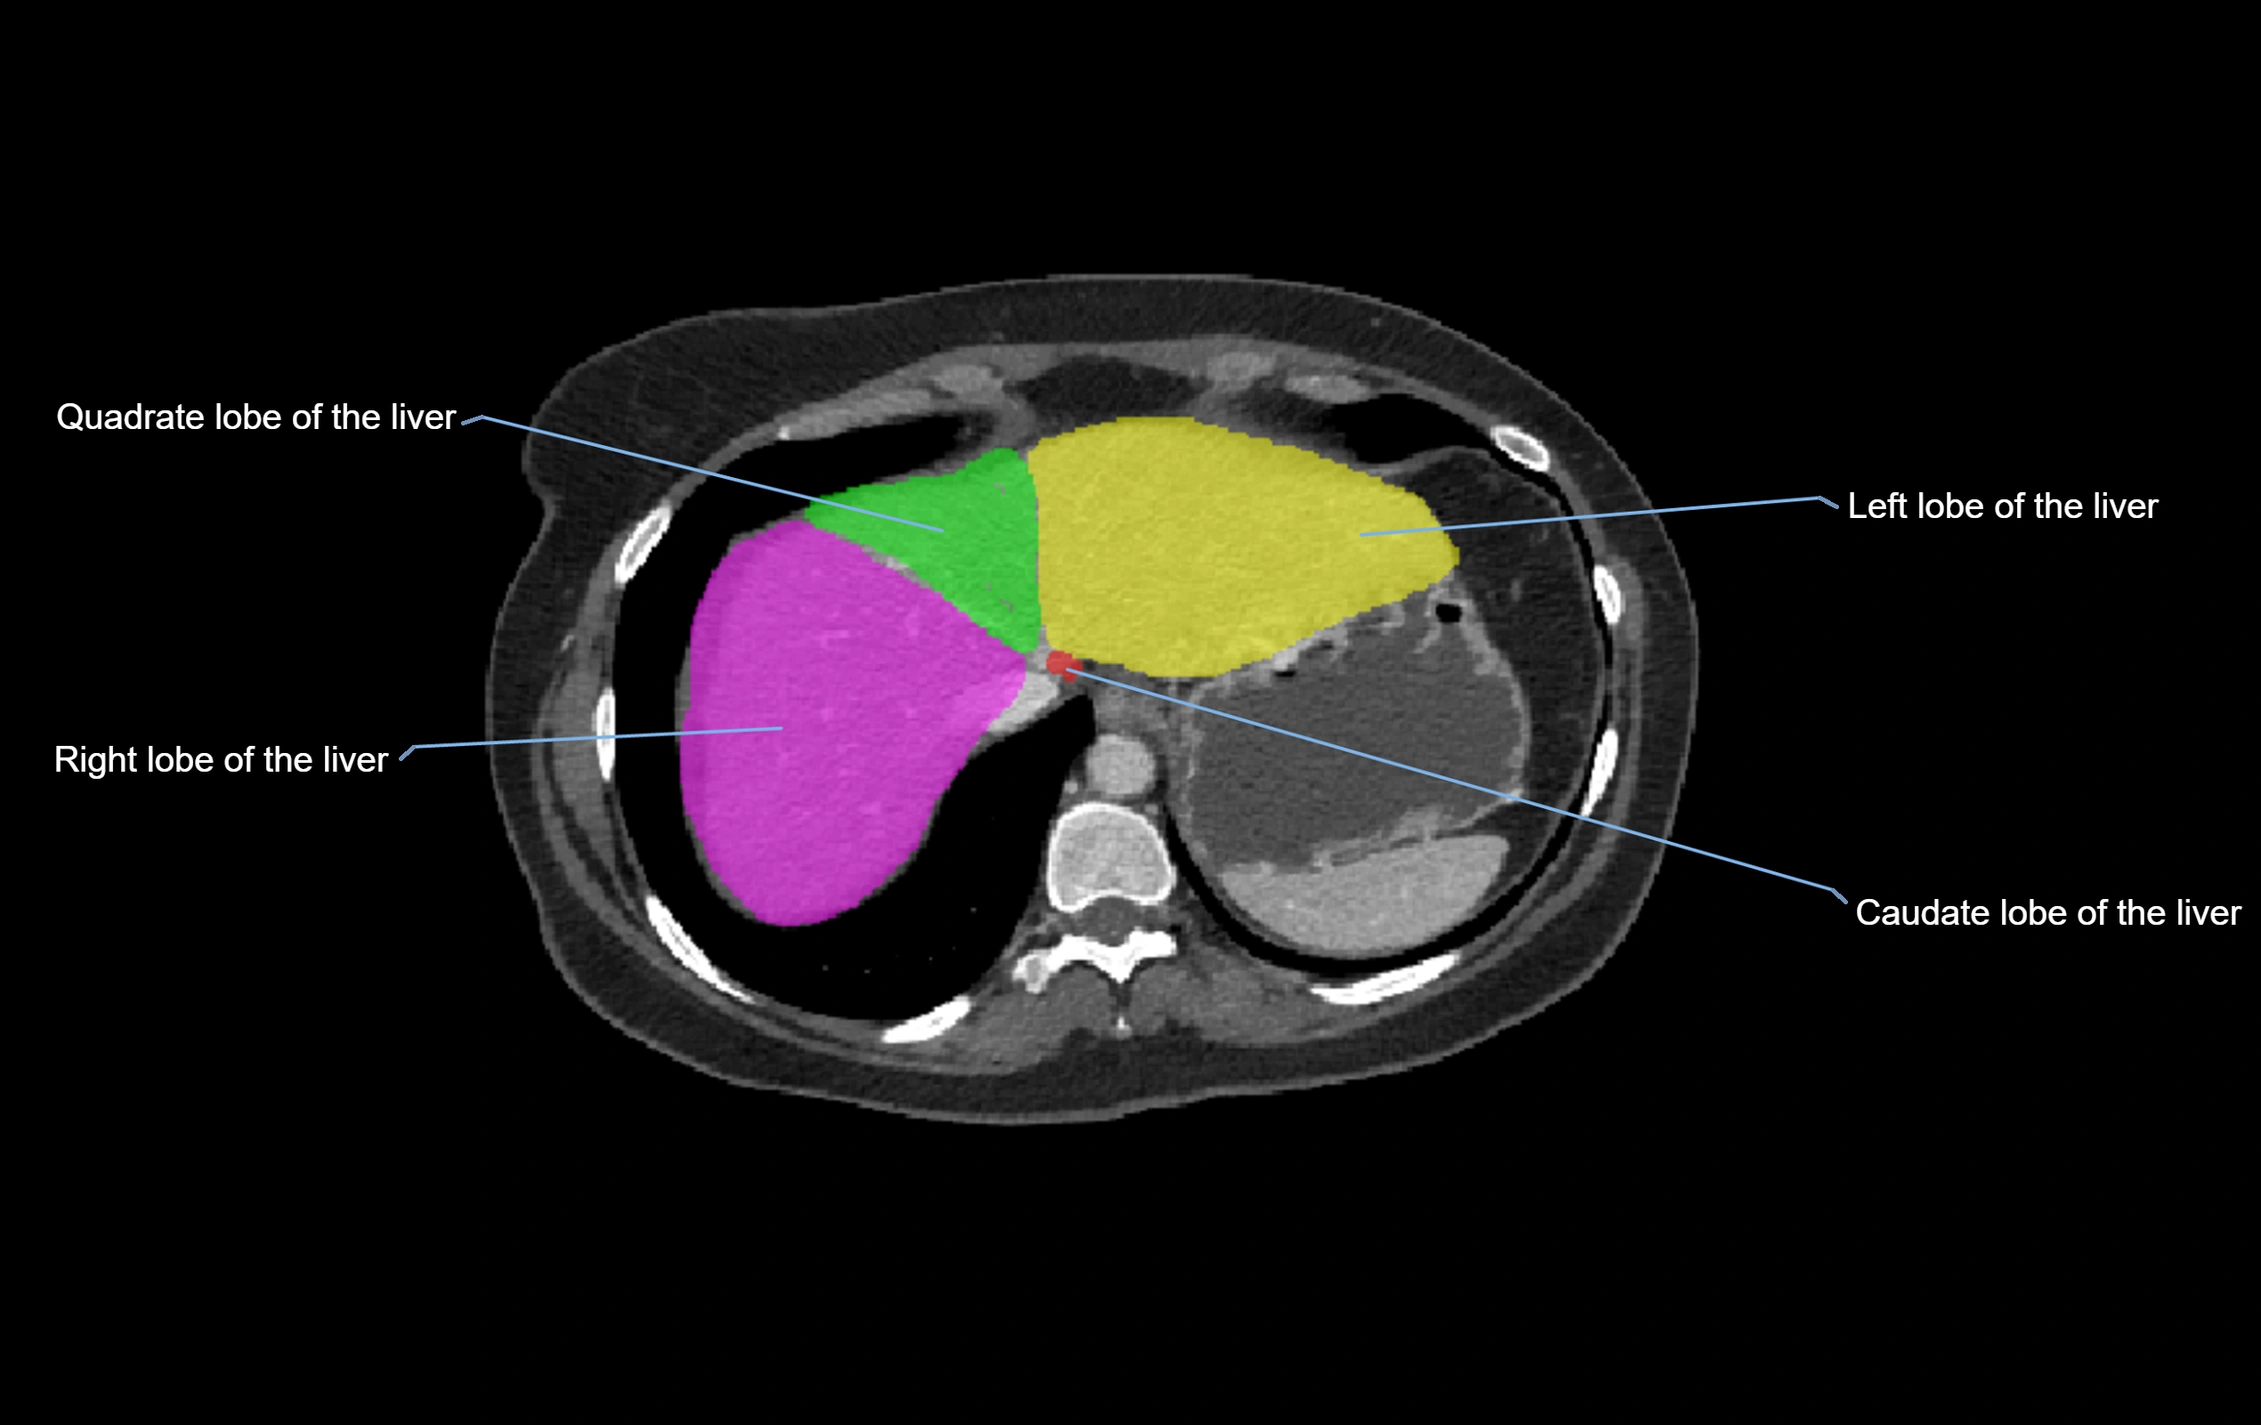

CT Image

image